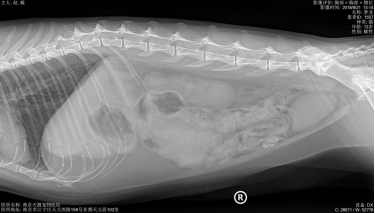

主人叙述2年前体检时,B超检查查出腹腔肿物(直径约6.1CM,场回声团块 ),主人当时选择保守治疗。每天吃完就吐,频繁的呕吐(3-4),导致梦龙体重急剧下降,主人十分担心。到我院初步诊断发现腹部触诊敏感,前腹部大肿物明显,为了准确评估梦龙的情况,医生对梦龙做了X光、生化和B超检查,进一步了解梦龙的身体情况。

X光显示肺纹理增粗,其他未见异常。